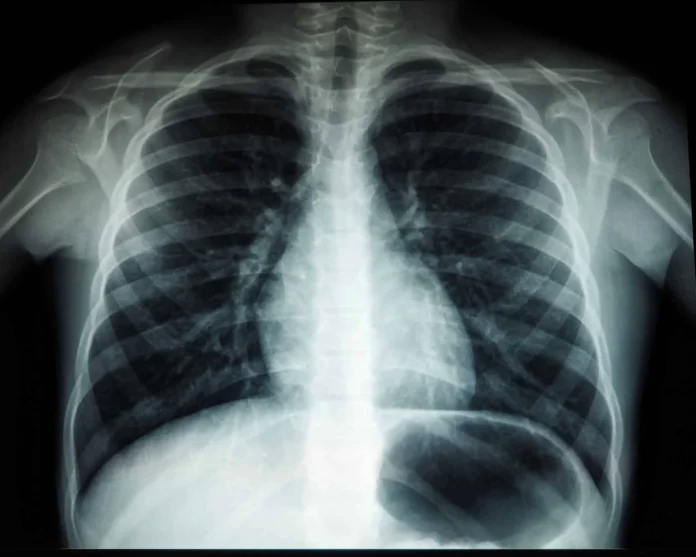

Идиопатическая легочная артериальная гипертензия (ИЛАГ), являясь малоизученным заболеванием, сопровождается сужением легочных сосудов и утратой их эластичности. Важную роль в ее развитии играют изменения в гене BMPR2, отвечающем за регулировку клеточного роста в сосудистых стенках. Возникающие мутации препятствуют нормальной работе рецептора, что ведет к утолщению артерий, снижению их просвета и замедлению кровотока, усиливая нагрузку на сердце и уменьшая поступление кислорода в кровь.